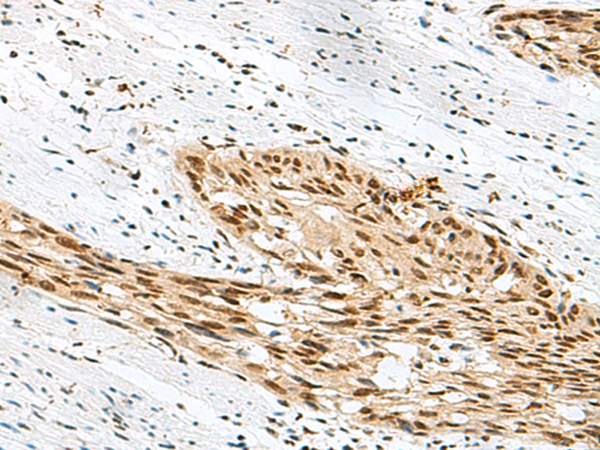

IHC positive control:

Human lung cancer and Human prostate cancer

IHC Recommend dilution:

50-300